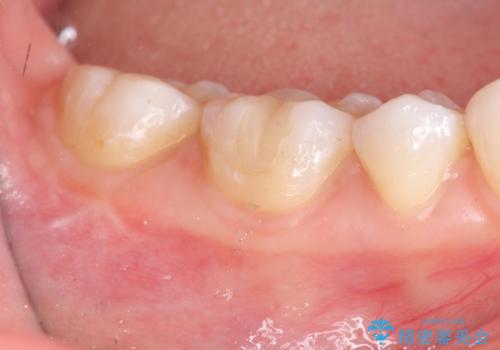

- 14万円 セラミックインレー×2費用は治療当時の料金となります

審美性を回復し、虫歯も予防のできる精密なセラミックインレーを装着することができました。